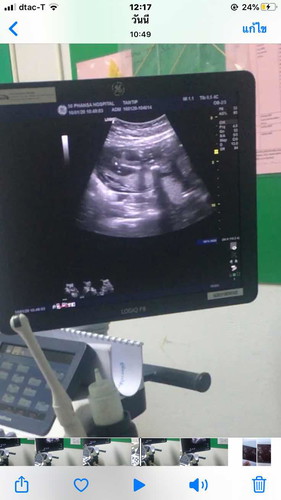

เพศ

แม่ๆคิดว่า ญ หรือ ช ค่ะ ????

ไม่เห็นจ้ารูปนี้

หมอว่ายังไงอะคะ